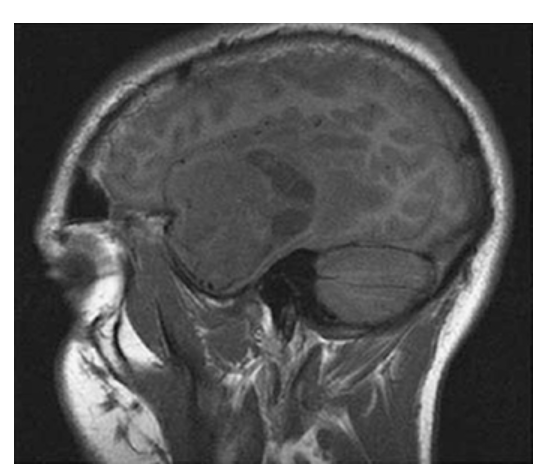

Astrocytoma. Sagittal T1W image shows an isointense mass in the left temporal lobe with surrounding low signal edema.